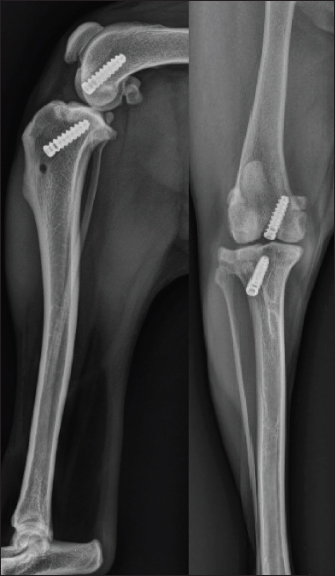

Postoperative radiographs showed a satisfactory position of the tunnels and a good implantation of the interference screws along the drilling axes (Fig. 5).

Fig. 5. Immediate postoperative radiographic views of the dog's right pelvic limb from side (left) and front (right).